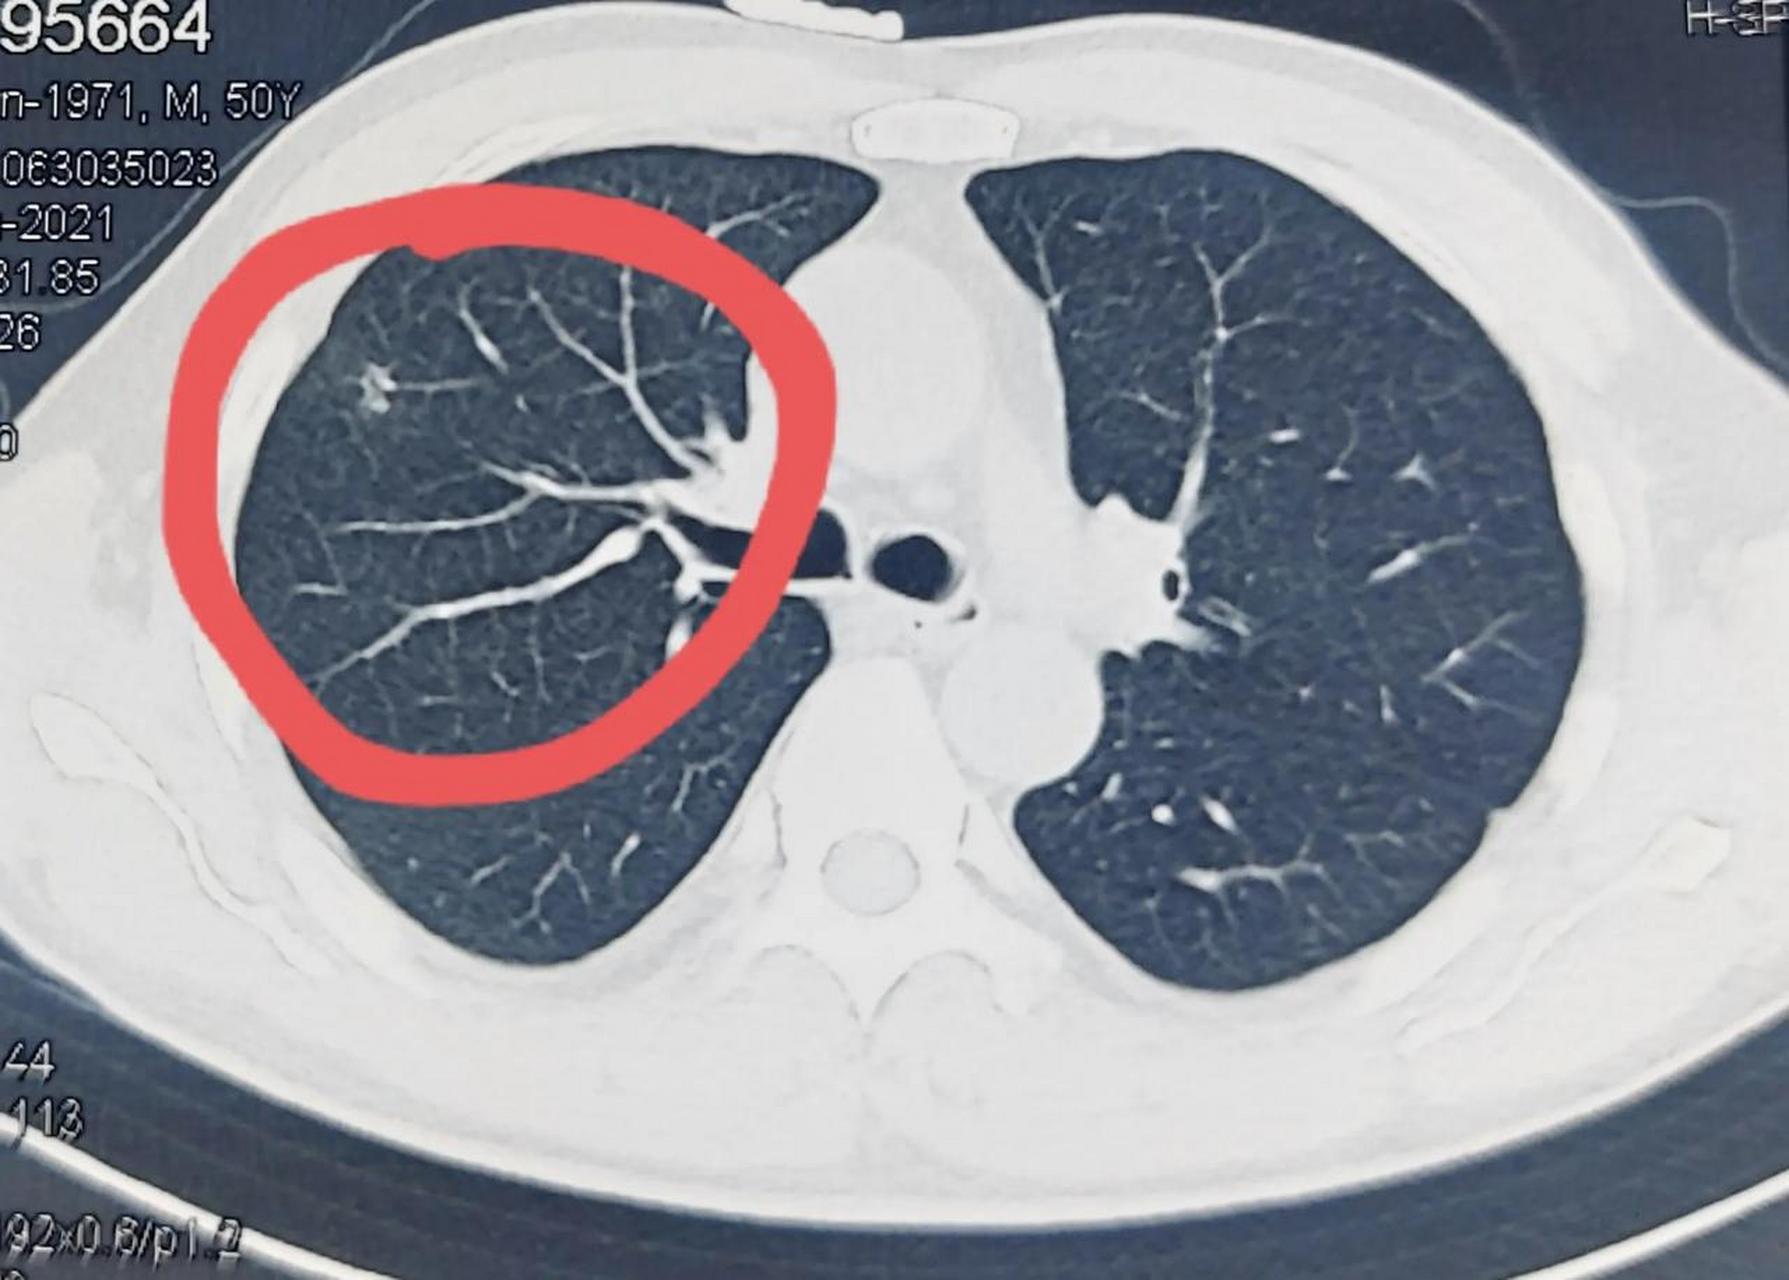

问诊分析:年仅15岁,肺结节(考虑早期肺癌)已经20个月!

50岁女性体检发现肺结节!深夜发帖,请各位影像大佬解答下疑惑?